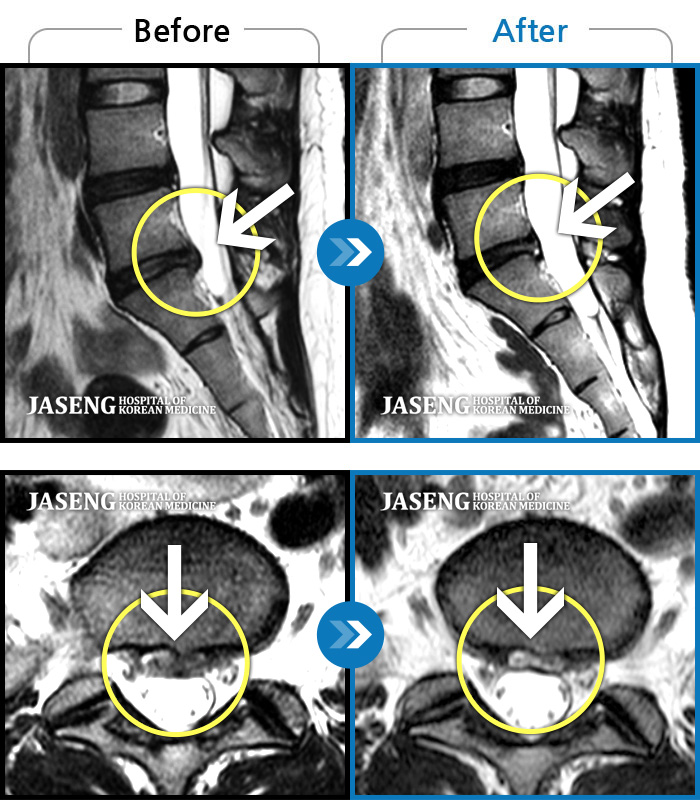

허리디스크

도움받은 사례

강남 · 이남우 원장

허리 통증과 함께 발끝 저림이 1년 이상 되었으며 최근 1-2개월 사이에 증상이 급격히 심해져 우측 다리 앞 뒤가 당기고 힘이 빠져 본원에 내원함

촬영시기

2023.11.20 ~ 2024.08.12